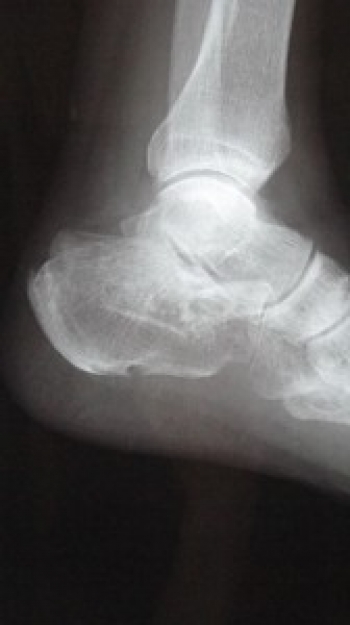

ìû¹ü¹üÀÞ

ìû¹ü¤Ï­º¬¹ü¤ÎÃæ¤ÇºÇÂç¤Î¹ü¤Ç¡¢Êâ¹Ô»þ¤ËºÇ½é¤ËÀÜÃϤ¹¤ëÉô°Ì¤Ë°ÌÃÖ¤·¡¢Â­º¬¹ü¹üÀÞÃæ¤â¤Ã¤È¤âÉÑÅÙ¤¬¹â¤¤¡£

µ÷¹ü¤Ê¤É¤ÈÊ£»¨¤Ê·ÁÂ֤δØÀáÌ̤òÍ­¤¹¤ë¤¿¤á¡¢¹üÀÞ¤¬À¸¤¸¤ë¤È´ØÀáÆâ¹üÀÞ¤òµ¯¤³¤·¤ä¤¹¤¤¡£

¤Þ¤¿¡¢¼þ°Ï¤òç§¡¦¿À·Ð¤â¿¿ô·Ð²á¤·¤Æ¤ª¤ê¡¢¤½¤Î¤¿¤á¸å°ä¾É¤âµ¯¤³¤·¤ä¤¹¤¤¡£

ȯÀ¸µ¡½ø¤Ë¤è¤êÀÔÄÇÄÇÂΰµÇ÷¹üÀÞ¤â¹çÊ»¤¹¤ë¤³¤È¤¬¤¢¤ë

ʬÎà¤Ï¡¢´ØÀá³°¹üÀÞ¡¢´ØÀáÆâ¹üÀÞ¤¬¤¢¤ë¡£

ìû¹ü¹üÀÞ¤ÎȯÀ¸µ¡½ø

¹â½ê¤è¤êžÍî¤äÈô¤Ó¹ß¤ê¤Ë¤è¤ëľã³°ÎÏ

¤Þ¤ì¤Ë²¼ÂÜ»°Æ¬¶Ú¤Î¼ý½Ì¤Ë¤è¤ë¥¢¥­¥ì¥¹ç§¤ÎµÞ·ã¤Ê¸£°úÎϤˤè¤Ã¤ÆÇíÎ¥¹üÀÞ¤¬µ¯¤³¤ë¡£

ìû¹ü¹üÀޤξɾõ

­¡´µÂ¦»è¤ÇΩ¤Ä¤³¤È¤¬½ÐÍè¤Ê¤¤

­¢ìûÉô¤Î¼ðı¤¬¤â¤Ã¤È¤â¶¯¤¯¡¢Â­´ØÀáÉô¤Þ¤ÇÇȵڤ¹¤ë

­£Èé²¼½Ð·ì¤Ïìûä­Äì¤ËµÚ¤Ö

­¤µ÷ÂÜ´ØÀá¶þ¿­±¿Æ°¤Ï²Äǽ¤Ç¤¹¤¬¡¢¹üÀÞ¤¬µ÷ìû´ØÀá¤ËµÚ¤Ö¤È­¤Î²óÆâ²ó³°±¿Æ°¤¬ÉÔ²Äǽ

­¥ìû¹ü¹üÂÎÉô¤Èδµ¯Éô¤Î¹ü¤ÎÃǤ¿¤ì¤¿¤â¤Î¤Ï¡¢Â­¤ÎÄì¶þ¤¬¶¯¤¯À©¸Â¤µ¤ì¤ë¡£

ͽ¸å¤Ï¡¢ÊÑ·Á¼£Ìþ¡Ê²£·Â¤ÎÁýÂ硢٨ʿ­¡Ë¡¢ç¤¹ü¶Úç§¾ä±ê¡¢ÊÑ·ÁÀ­´ØÀá¾É¡¢ËýÀ­Éâ¼ð¡¢¥º¥Ç¥£¥Ã¥¯¹ü°Ñ½Ì¡¢¥¢¥­¥ì¥¹ç§¼þ°Ï±ê¤Ê¤É¤Ë¤è¤ë¤µ¤Þ¤¶¤Þ¤Ê²Ù½Å»þáÖÄˤò»Ä¤·¤ä¤¹¤¤¤Ç¤¹¡£